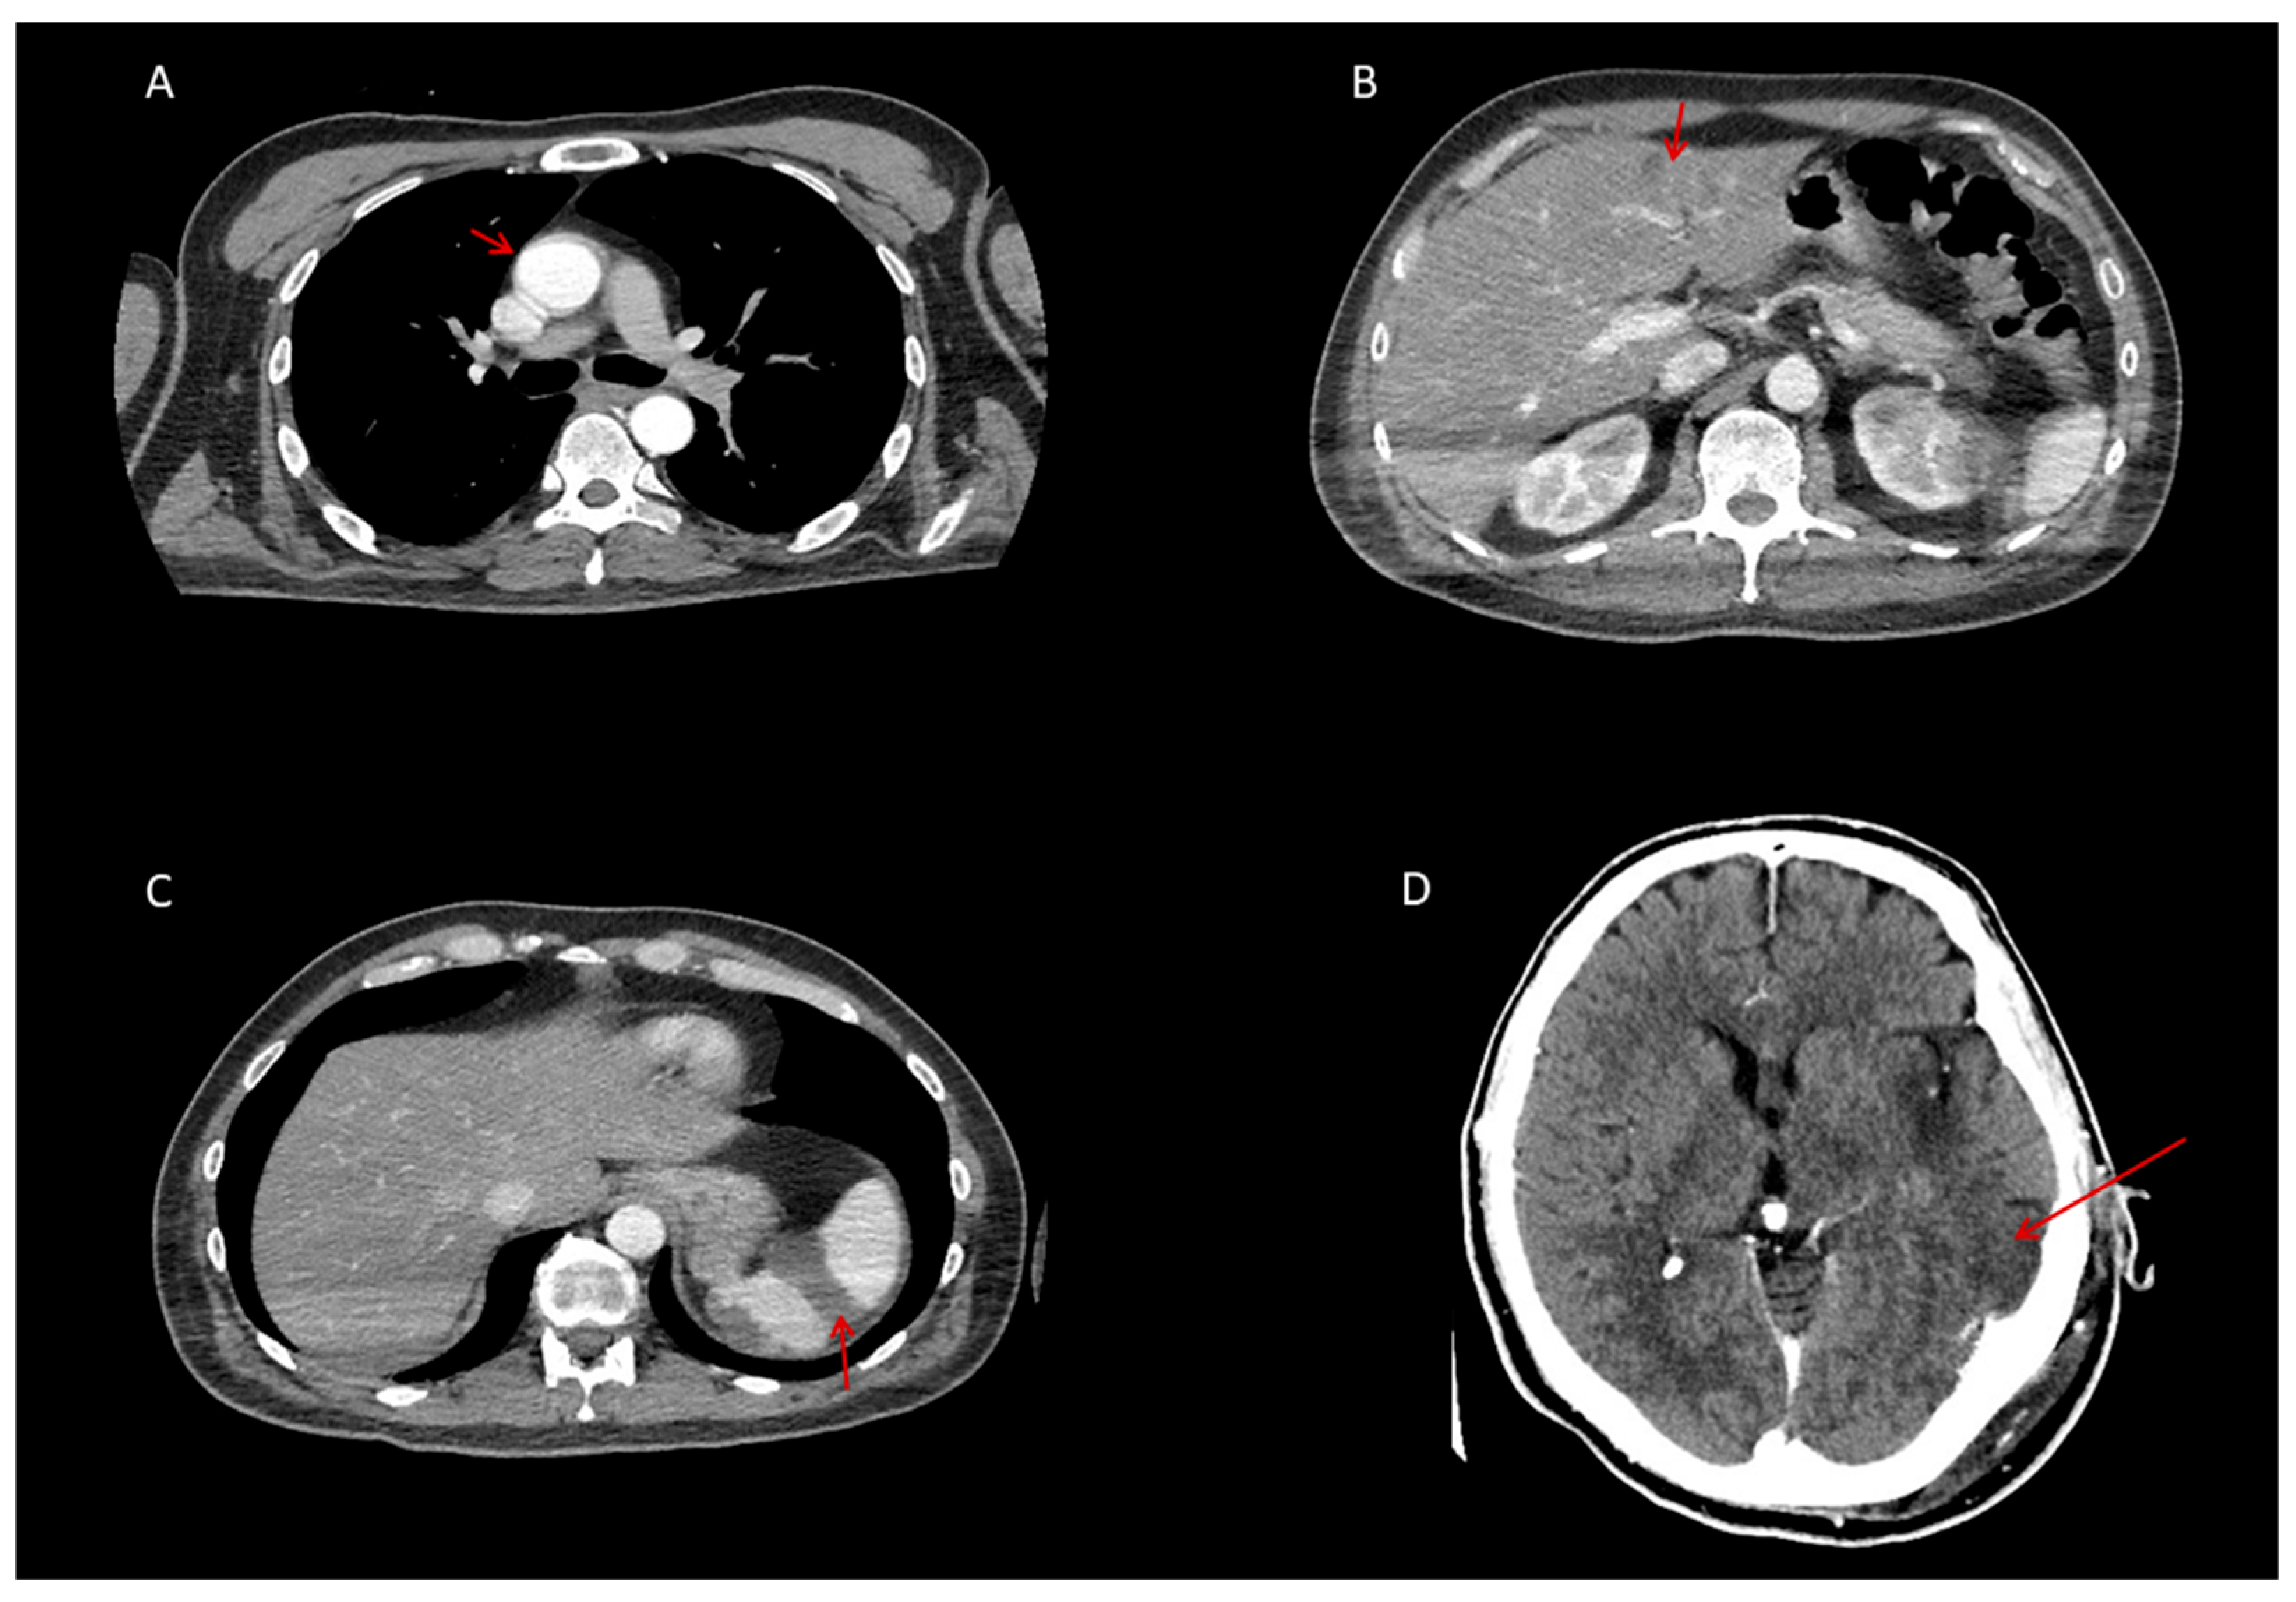

2.4. Neurological and Thrombotic Complications